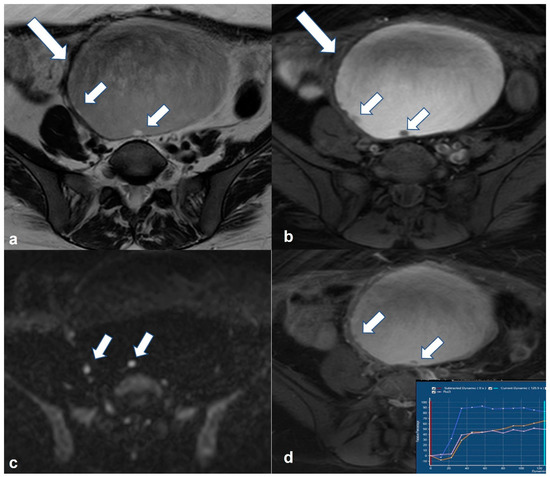

2.4.3. Dysgerminoma

2.5. Pregnancy